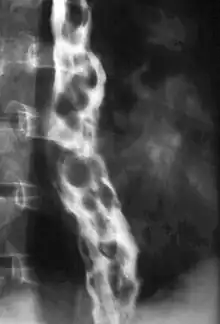

X-ray of a person with dilated, snake like varicose veins in their esophagus secondary to pulmonary hypertension.

In ideal circumstances, people with known varices should receive treatment to reduce their risk of bleeding.[8] The non-selective β-blockers (e.g., propranolol, timolol or nadolol) and nitrates (e.g., isosorbide mononitrate (IMN) have been evaluated for secondary prophylaxis. Non-selective β-blockers (but not cardioselective β-blockers like atenolol) are preferred because they decrease both cardiac output by β1 blockade and splanchnic blood flow by blocking vasodilating β2 receptors at splanchnic vasculature. The effectiveness of this treatment has been shown by a number of different studies.[9]